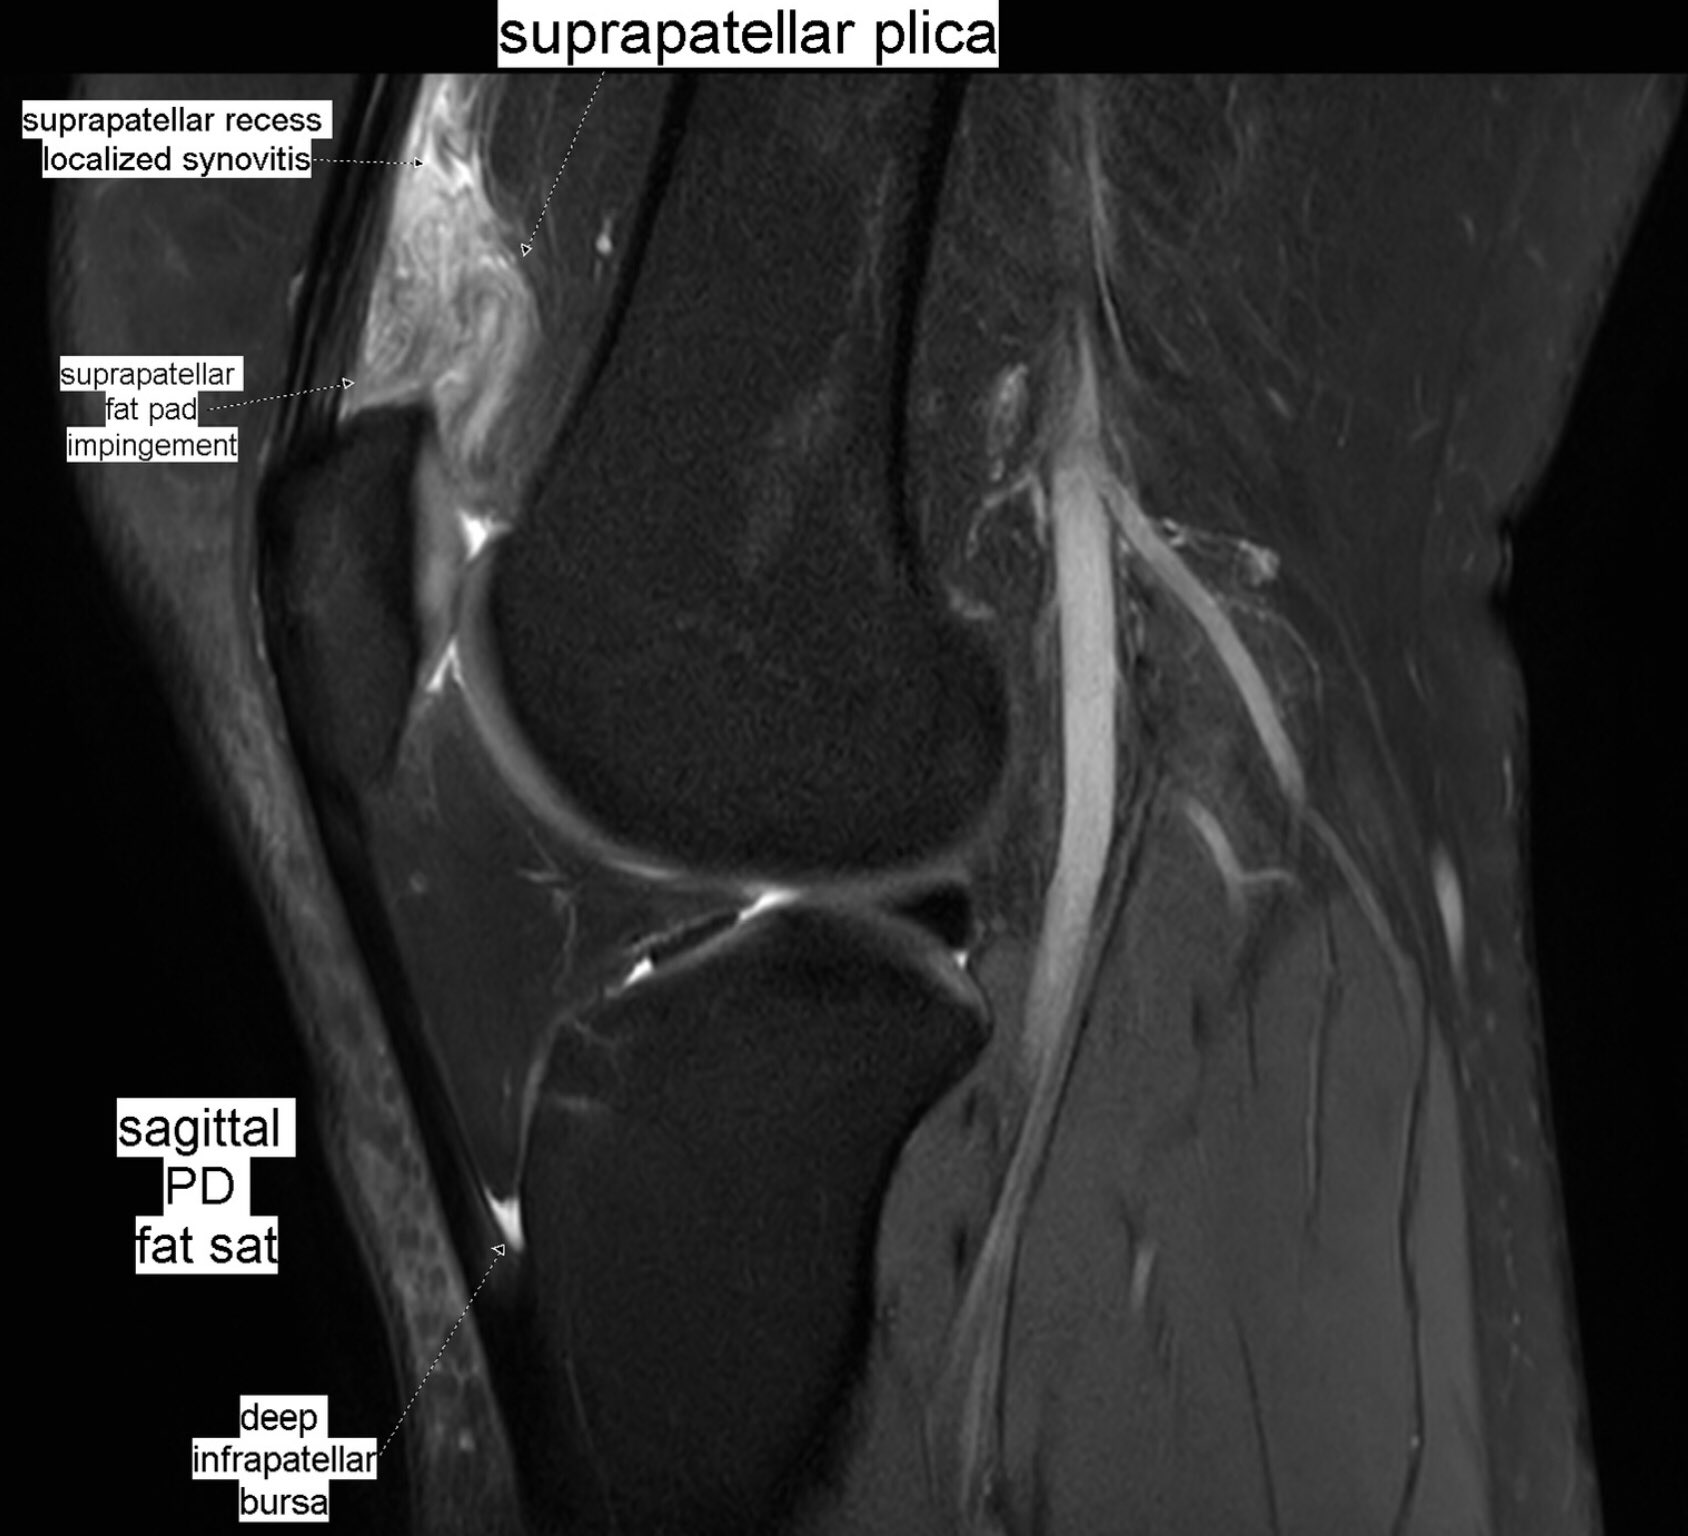

Benoit Rizk A Twitter Patient With Anterior Knee Pain Localized Synovitis Of Suprapatellar Recess And Suprapatellar Fat Pad Impingement Syndrome Secondary To A Suprapatellar Plica Suprapatellar Plica Syndrome Mskrad Knee Orthopaedics Radiology

Hypertrophy of infrapatellar fat pad. Infrapatellar fat pad syndrome can happen for a number of reasons. In this syndrome the posterior border of the anterior suprapatellar quadriceps fat pad is high signal on PD MRI and convex with a mass effect upon the suprapatellar.

This video demonstrates manual therapy techniques for the patella and knee using the Motion Guidance Contact Pad. Front aspect knee pain. The term quadriceps fat-pad impingement has been used to describe an inflammatory process within the anterior suprapatellar fat manifested on MRI as high T2 signal low T1 signal and mass effect on the quadriceps tendon.